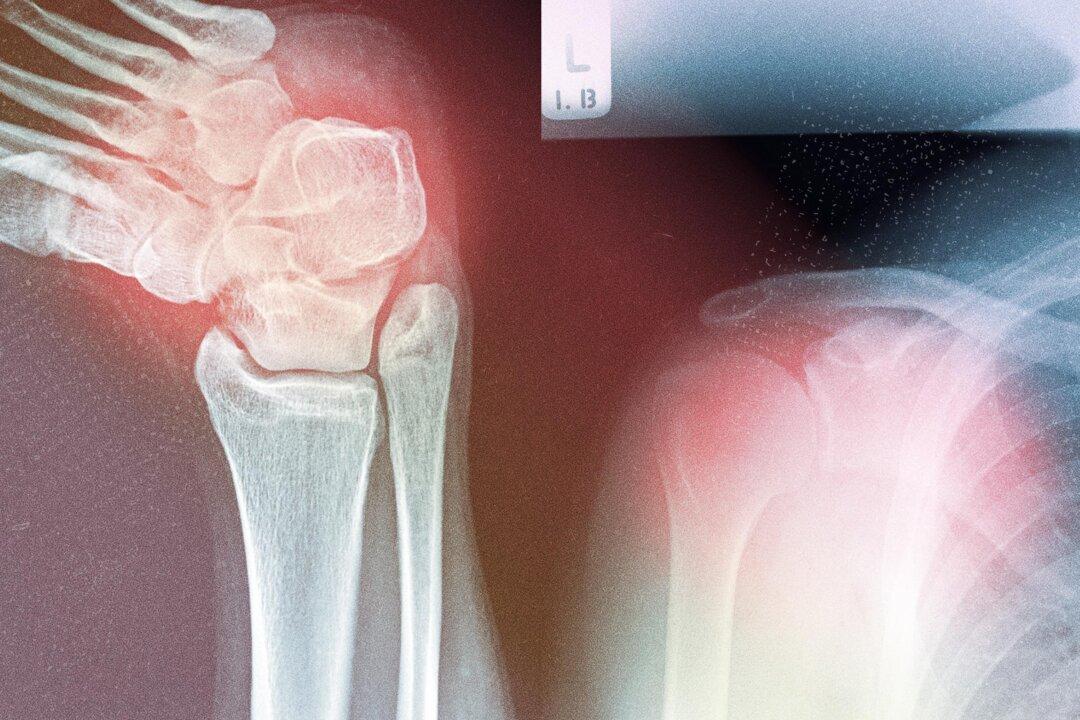

Someone with back pain might receive painkillers from his or her primary care physician, then be referred to a physiotherapist, and possibly sent for a scan if the pain continues.